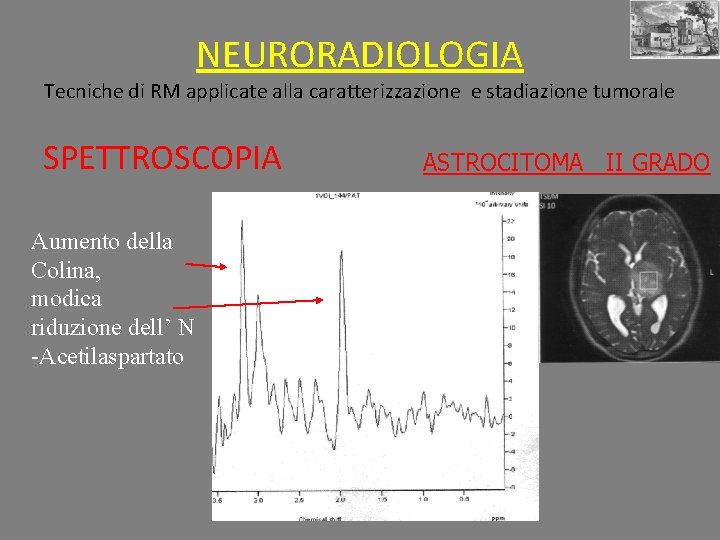

NEURORADIOLOGIA Tecniche di RM applicate alla caratterizzazione e stadiazione tumorale SPETTROSCOPIA Aumento della Colina, modica riduzione dell’ N -Acetilaspartato ASTROCITOMA II GRADO